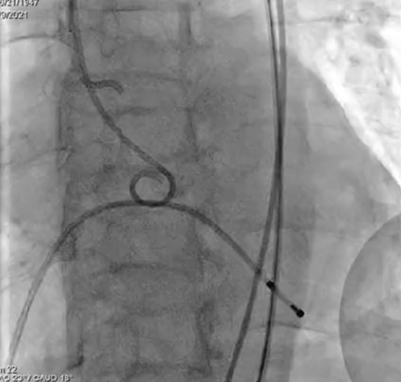

输送系统输送至窦底,行主动脉根部造影,借助无冠窦猪尾造影定位,由于该患者基础心率较缓慢,瓣膜无起搏顺利释放。

释放

术后心电监护未见传导阻滞。即刻造影和测压显示基本无压差和无反流。